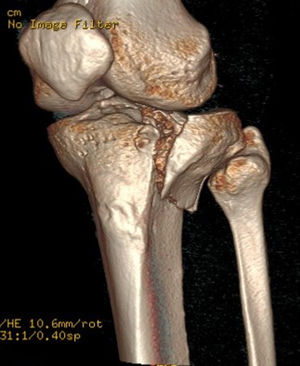

En el estudio de TC se hizo una adquisición volumétrica en un equipo multicorte a 0,6mm con posteriores reconstrucciones multiplanares de 1,5mm de espesor y 1,0mm de intervalo. En la reconstrucción en el plano coronal se analizó el punto de mayor depresión de la fractura en mm que se corresponde con el escalón articular máximo y la anchura máxima/diámetro transversal en mm; en el plano sagital se midió el diámetro máximo anteroposterior en mm del escalón articular y la caída máxima (slope) de la meseta tibial externa en grados (fig. 3). En el post-procesado en el plano axial se delimitó el contorno de la fractura y se calculó el área afecta en cm2, así como el diámetro mayor anteroposterior y la anchura máxima en mm (diámetros máximos anteroposterior y transversal) (fig. 4).